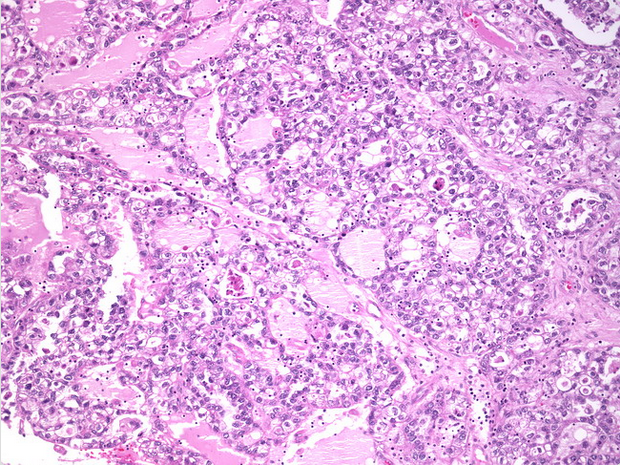

CARCINOMA ENDOMETROIDE DE OVARIO Binipatia e higienismo 😈

File:Endometrial adenocarcinoma 2 .jpg 😈